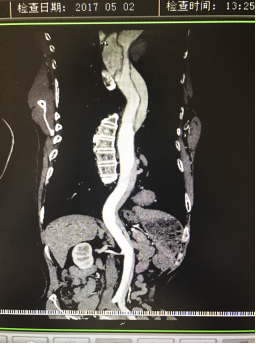

5月2號劉大伯照常早起干活,突然胸部劇烈疼痛,難以忍受,全身大汗,同時伴有右上肢發(fā)涼,他心想這次心絞痛比之前嚴(yán)重的多啊,趕緊叫上孩子到吉林國文醫(yī)院心血管內(nèi)科住院,患者長期高血壓病史,血壓一直控制不理想,大夫給他做了檢查,測左上肢血壓:82/45mmHg,右上肢血壓測不出,心率52次/分,右側(cè)肱動脈、尺動脈、橈動脈搏動消失,左側(cè)股動脈搏動較右側(cè)弱?!霸懔耍p側(cè)血壓差別這么大,是不是主動脈夾層了?”,接診大夫趕緊找來李主任,李主任反復(fù)詢問患者病情,表情突然凝重起來,患者胸痛這么明顯,血壓低的厲害,主動脈夾層的可能性很大。二話不說,李主任立即聯(lián)系影像科的醫(yī)生準(zhǔn)備做主動脈CTA,移動患者做檢查的過程大夫們非常小心,嚴(yán)密監(jiān)測患者血壓變化情況。兩個小時后結(jié)果出來了,主動脈夾層從升主動脈一直撕裂到左側(cè)髂總動脈?。?!